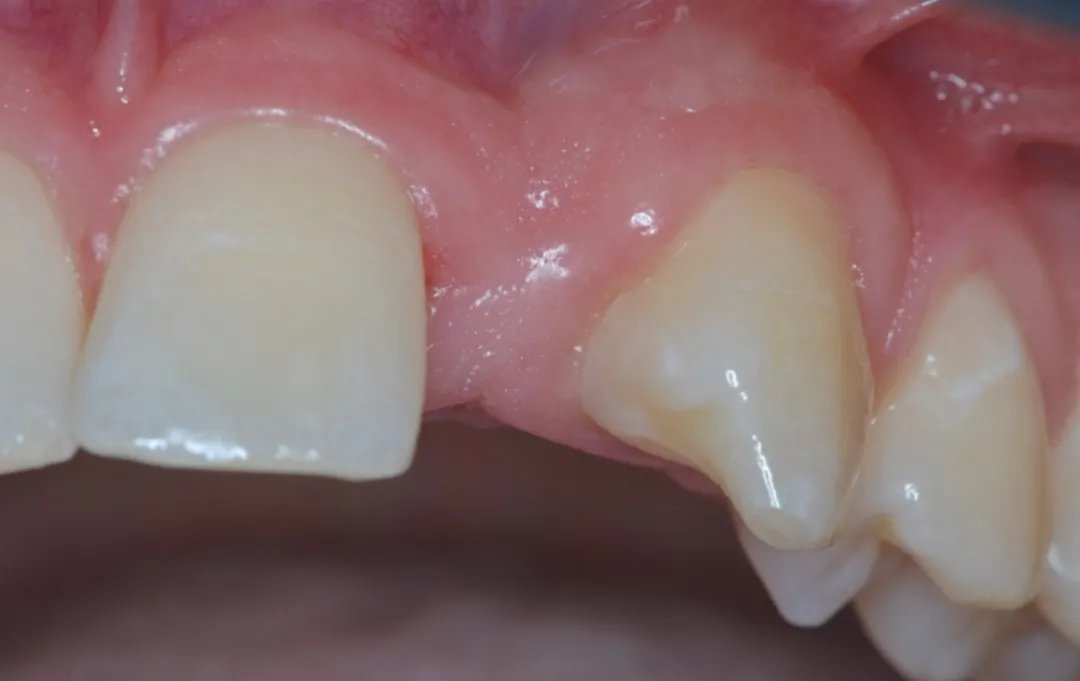

3 号病例 - Patrick EXBRAYAT 医生(图 36 至 49)

女性患者,侧切牙 12 发育不全,长期使用临时修复手段。

图 37 :术前临床情况。

图 38 :拔牙后种植位点。